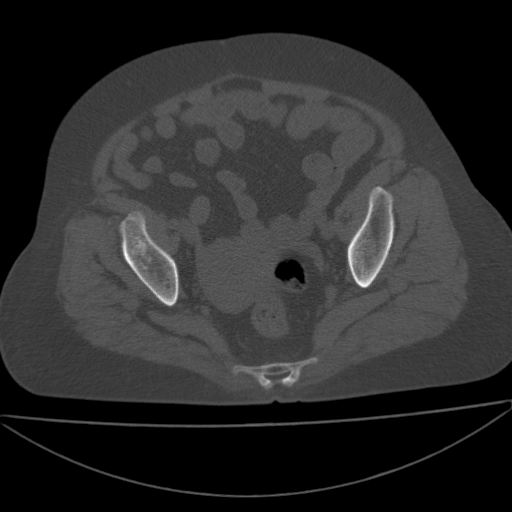

以下是引用王显瑞在2009-4-23 16:45:00的发言:[br]考虑股骨颈陈旧性骨折,股骨头缺血型坏死

以下是引用余辉在2009-4-23 17:08:00的发言:[br]考虑右髋关节退行性变.股骨颈改变考虑陈旧性骨折可能,股骨头顶部关节面下似有透亮区,股骨头皮质环增厚,考虑有股骨头坏死